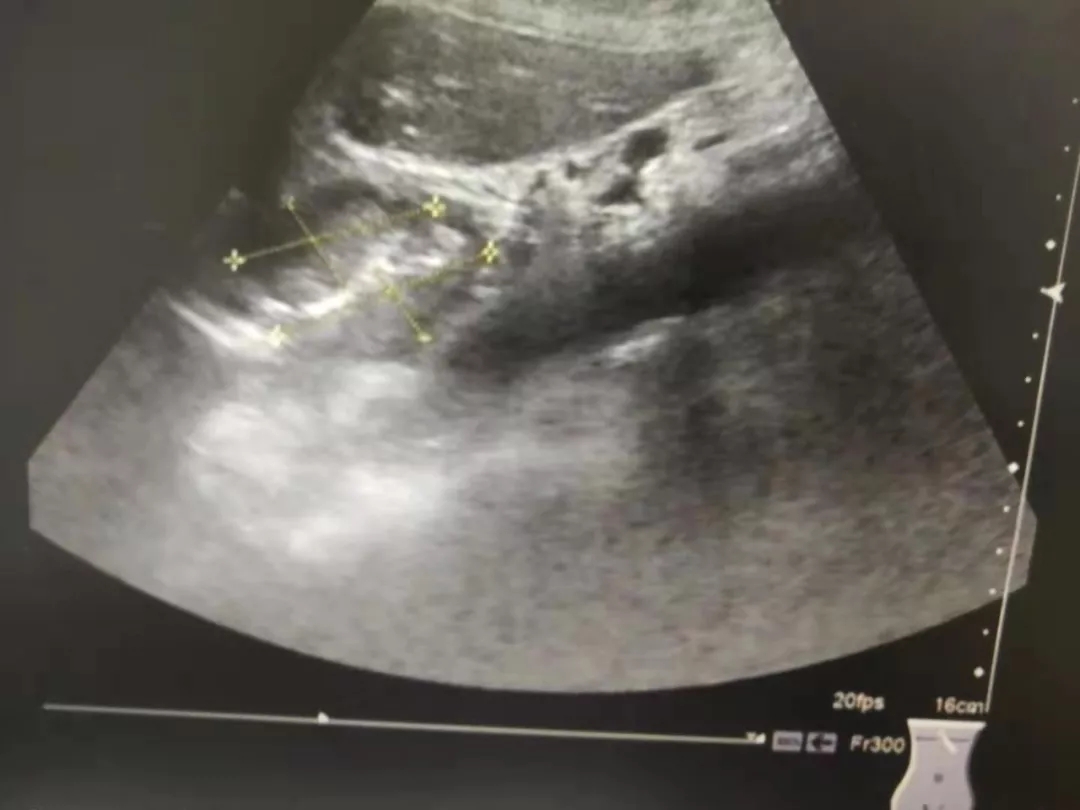

胃贲门癌